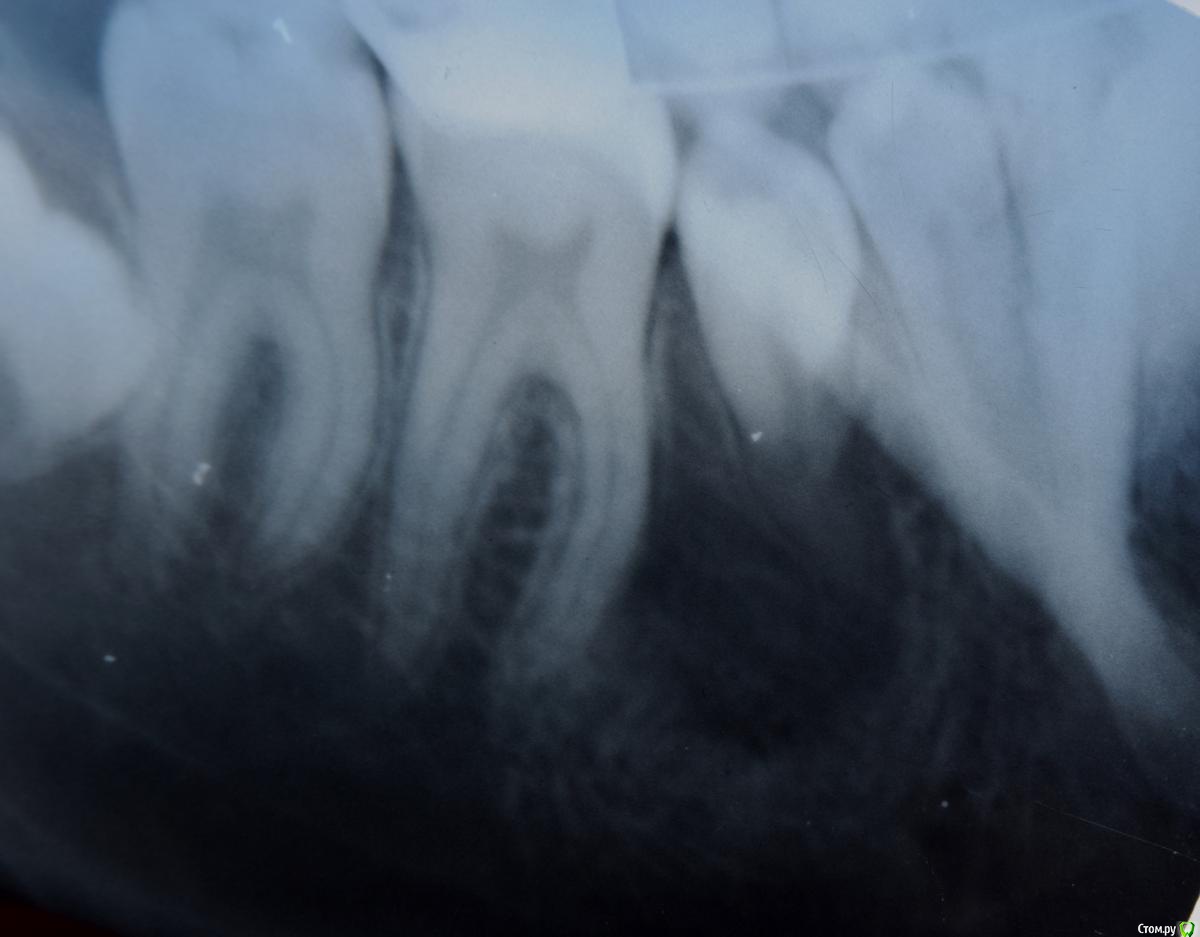

Kovalov Igor Опубликовано 14 июля, 2015 Автор Поделиться Опубликовано 14 июля, 2015 (изменено) Через год ОПТГ снимок Изменено 14 июля, 2015 пользователем Kovalov Igor Ссылка на комментарий